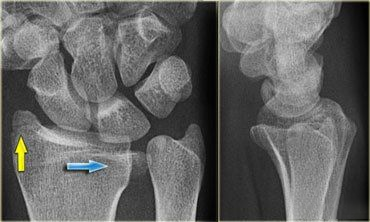

(1)Essex-Lopresti 骨折

是桡骨头骨折伴有下尺桡关节脱位,导致骨间膜损伤,桡骨短缩。此种损伤,桡骨头骨折的诊断往往是明确的,容易忽视的是下尺桡关节脱位,特别是早期,下尺桡关节的症状不明显,X 线表示也不明显。

前后位(A)和侧位(B)示桡骨头关节内骨折(白色实线箭头);(C~E)伤后 1 个月复诊,患者诉腕关节疼痛,X 线(C,D)发现下尺桡关节脱位,(E)CT 进一步证实损伤的存在。